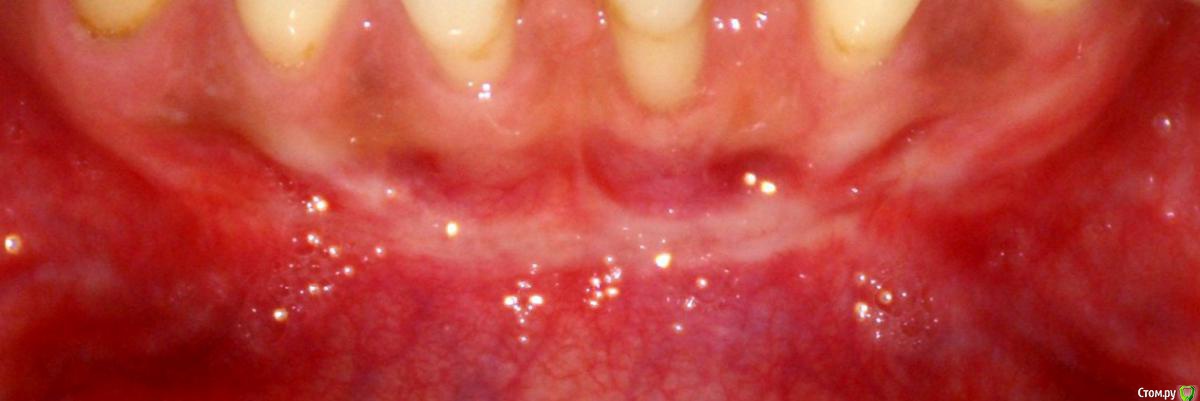

Irina_S Опубликовано 15 июня, 2017 Поделиться Опубликовано 15 июня, 2017 Здравствуйте, уважаемые специалисты! Заранее прошу прощения за не слишком качественные фото! Почти восемь месяцев назад мне была сделана вестибулопластика на нижней челюсти.За пять дней до операции ситуация во рту выглядела так: Для проведения операции были такие показания: Вот ещё описание самой операции, которая была 24 октября 2016 г.: Через шесть дней после операции: Ещё через шесть дней, 5 ноября: Прошла ещё неделя, 12 ноября: Следующий раз фото, к сожалению делалось через три с лишним недели, 4 декабря, в разных ракурсах: После этого визуальные изменения касались только уменьшения белёсых мест от разреза.Вот состояние на 10 июня этого года с разными вариантами оттягивания губы: По результатам заживления я не вижу разницы в глубине преддверия, ради чего и проводилась операция.К тому же всё время с момента операции присутствуют стягивающие ощущения и ощущение инородного тела в подбородке. Ответьте, пожалуйста, правильно ли была сделана операция вестибулопластики?Спасибо за внимание! Ссылка на комментарий

Irina_S Опубликовано 16 июня, 2017 Автор Поделиться Опубликовано 16 июня, 2017 у Вас образовались тяжи в области клыков,которых раньше не было. А можно Вас попросить уточнить, что Вы называете тяжами?Под номером 1, под номером 2 или и то и другое вместе? Ещё вот такая хронология: 24 октября была сделана вестибулопластика, 28-го сняли швы, до 13 ноября я касалась кончиком языка "кармана" в глубине линии разреза, отметила это на фото, чтобы было понятно, о чём речь. 14 ноября проводилась обработка зубов с помощью аппарата Вектор и были заложены саморассасывающиеся лечебные повязки на обе челюсти, в том числе и в этот "карман". В этот день увидела, что "карман" визуально склеился из-за заложенной повязки, и я перестала на несколько дней делать упражнения с надуванием губ и касанием кончиком языка.А потом этот "карман" исчез и в итоге получилась поверхность, обозначенная на первой картинке под номером 3. Вопрос: мне не надо было допускать срастания двух поверхностей слизистой, чтобы этот "карман" остался, или его исчезновение и должно было произойти в процессе заживления? (думаю, что это срастание и вызвало ощущение стягивания и уплотнения внутри подбородка в виде инородного тела) Ссылка на комментарий

Irina_S Опубликовано 22 июня, 2017 Автор Поделиться Опубликовано 22 июня, 2017 Irina_S, какая цель Вашей темы???Вам уже ответили, что в рамках проведенного вмешательства все сделано правильно, результат есть, то что вас беспокоит не является осложнением, а сопутствует данное вмешательство. При многих звуках, в частности "б", "п", "о", "у", у меня выраженная физическая боль. Ухудшилась дикция в целом. Что-то в районе подбородка напрягается и не даёт безболезненно говорить. Никаких послеоперационных комментариев по этому поводу и по срокам дискомфорта мне не говорили. Поэтому я пытаюсь сама разобраться, понять, каким образом можно исправить ситуацию. Динамики никакой нет. Считать присутствующие ощущения нормальными не могу. Изменилась форма подбородка - об этом тоже никто не предупреждал. Вот и хочу получить информацию, должно ли вообще так быть, когда всё восстановится, и что можно делать, чтобы помочь себе в этой ситуации. Ссылка на комментарий